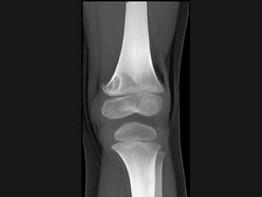

问题 男,12岁,大腿下部间歇性疼痛,劳累后加重,结合图像,最可能的诊断是 ( )

选项 A、邻皮质软骨瘤 B、非骨化性纤维瘤 C、干骺端结核 D、骨样骨瘤 E、纤维性骨皮质缺损

答案 E